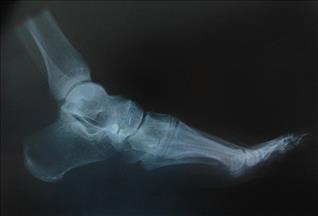

Eriyerek yok olma özelliğine sahip, sert ama hafif bir çeşit plastikten yararlanılarak üretilen implant, kemik içine yerleşiyor ve asıl kemiğin yeniden büyümesine destek oluyor. İmplantın çatısını oluşturan, kan akışına izin verecek şekilde bal peteği biçiminde üretilmiş plastik madde, hastanın kemik iliğindeki kök hücrelerin implanta tutunarak yeni kemik oluşturmasını sağlıyor. Daha sonra zaman içinde yavaş yavaş eriyerek yok olan plastik çatı yerini yeni oluşan kemiğe bırakıyor.